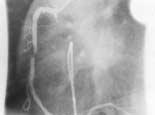

La intervención se realiza introduciendo un catéter con balón en la punta a través de la arteria femoral o braquial hasta la arteria coronaria lesionada. La insuflación del balón provoca la fractura y división de la placa y estira la pared arterial. Ello da lugar a un aumento del diámetro de la arteria coronaria, mejorando el flujo sanguíneo distal a la lesión.

En lesiones específicas (según valoración médica) se utilizan soportes intraco-

ronarios (STENT). Es posible proporcionar soporte mecánico a la pared arterial tras la angioplastia con balón por medio de un dispositivo protésico. Estos dispositivos están fabricados sobre todo de acero inoxidable quirúrgico, y sus dimensiones varían entre 15-30 mm. de longitud y 3-5 mm de diámetro después de la expansión.

Tras la angioplastia con balón de un ateroma coronario comprimible, se introduce hasta la zona un catéter de balón con un soporte plegado sobre él mismo. El soporte se despliega en la arteria coronaria al inflar el balón. El soporte permanece en el vaso al retirar el catéter. La presencia del soporte puede evitar el súbito cierre del vaso después de la ACTP y mejorar la permeabilidad a largo plazo del vaso coronario. Dada la naturaleza trombogénica del soporte, es necesaria la anticoagulación precoz (primeras horas) y antiagregación potente (AAS + Ticlopidina durante semanas) para pre-

venir la oclusión por trombosis del lugar donde se encuentra el soporte.

La reestenosis de la arteria coronaria puede ocurrir de manera brusca o algunos años después de que el paciente se haya sometido a la ACTP STENT. La mayoría de los casos de reestenosis surgen en los primeros 6 meses.